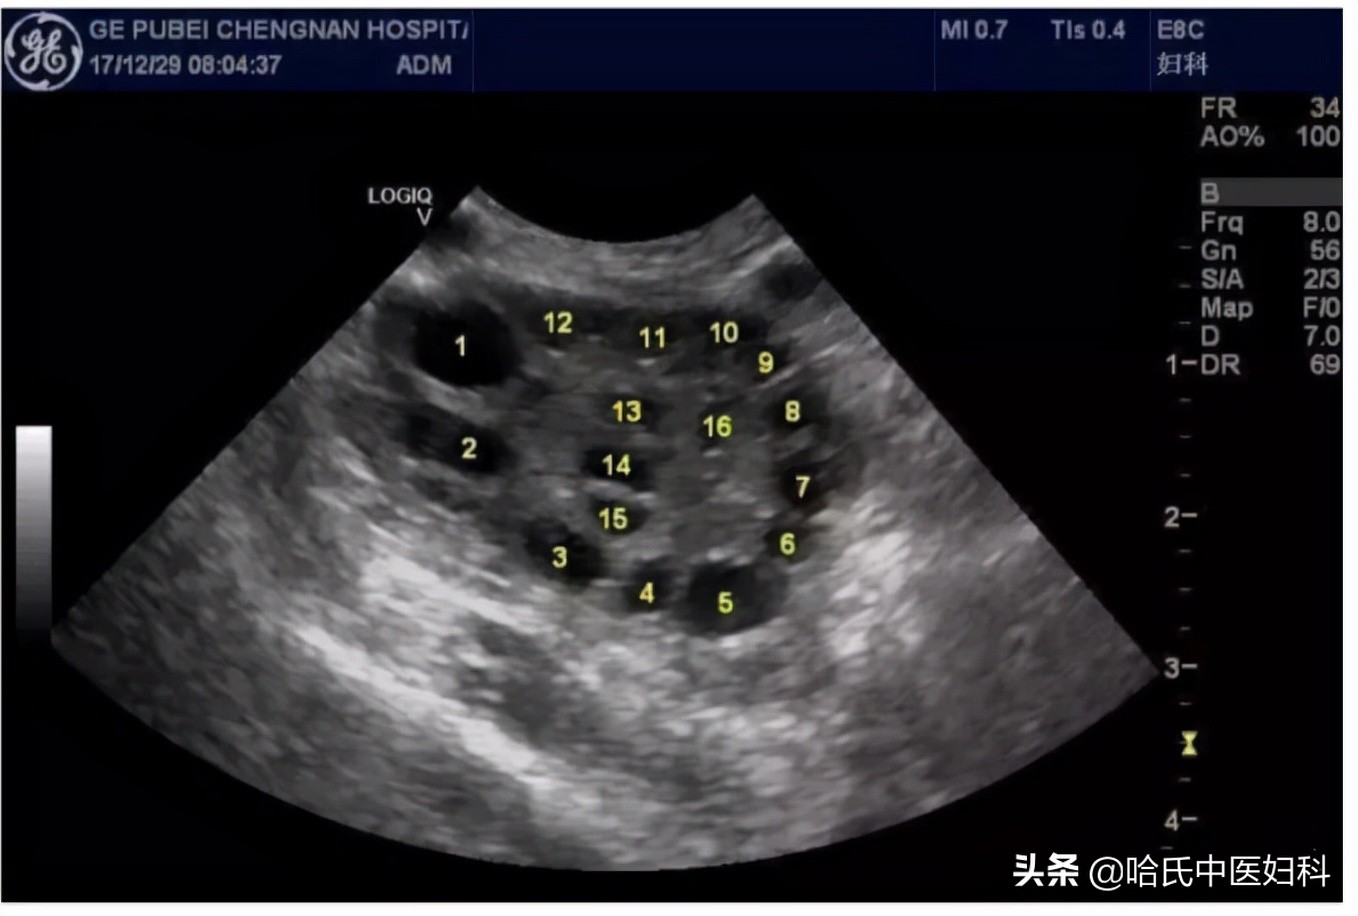

在排卵前卵泡处于生长期,由小变大,逐渐发展,如果按28天周期算,月经周期10天左右出现优势卵泡在12mm左右,然后以每天1.5-2.5mm的速度发展。

B超监测可以准确地看到卵泡的大小、发育情况并且预判排卵时间。一般于月经的第12天左右来院监测,根据卵泡发育情况医生会告知下次复查时间, 当卵泡大小在18-22mm则为成熟卵泡 ,排卵也就接近了,在观察到成熟卵泡后,建议再复查B超来观察卵泡是否已经排出。